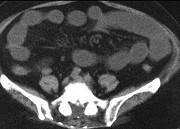

问题 男,30岁,有胆结石病史,近日腹痛、腹胀,CT检查如图,应诊断为 ( )

选项 A.胆石症 B.胆石性肠梗阻 C.肠结核 D.小肠克罗恩病 E.小肠淋巴瘤

答案 B